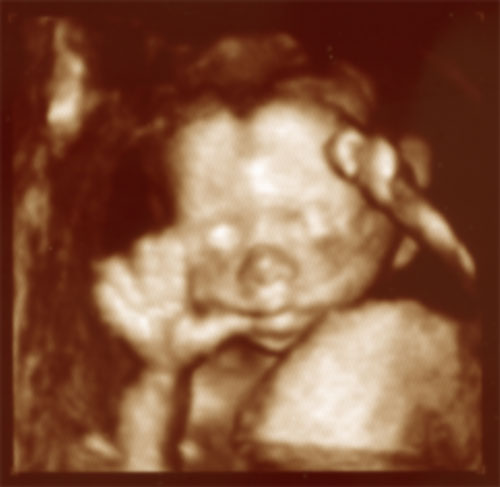

Little FunkyZorrette goes Vulcan...

Since both her parents are addicted to Star Trek, of course little FunkyZorrette  is also deeply into the Trekkie thing. The other day when her parents went to a 4D ultrascan she just had to do the Vulcan greeting.

Live long and prosper!

Btw...I'm almost 21 weeks old on this picture and I've seen my Mum buying some pink clothes :-).